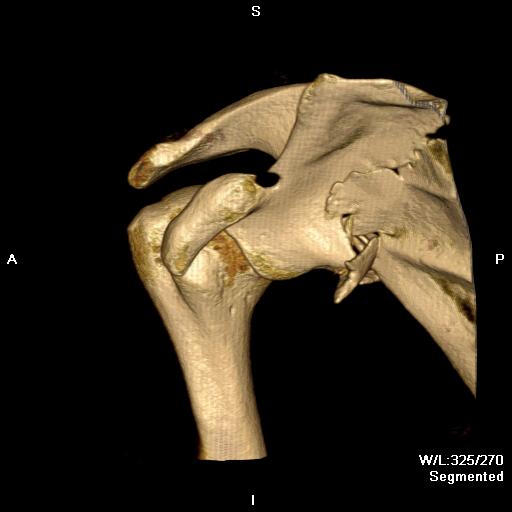

Combined Glenoid and Scapula Fractures

Case 1

- displaced glenoid fracture and neck fracture

- ORIF both through posterior / Judet approach